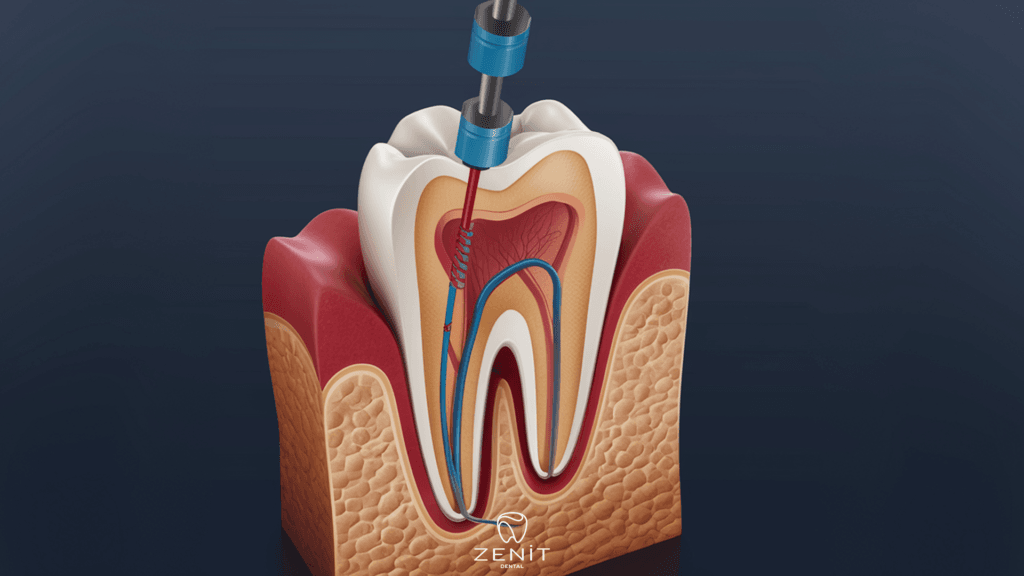

- Diş Çürükleri:

Diş çürükleri, bakterilerin diş minesini erozyona uğratması sonucu oluşan oyuklardır. Çürükler, bakterilerin dişin iç kısmına ilerlemesine ve burada enfeksiyon oluşturmasına zemin hazırlar. Çürüklerin tedavi edilmemesi durumunda, diş köklerine kadar ilerleyen enfeksiyonlar diş etlerinde şişmeye ve ağrıya yol açabilir.

- Tedavi Edilmemiş Diş Sorunlarının Giderilmesi: Diş çürükleri ve diğer sorunlar zamanında tedavi edilmelidir. Diş hekiminizin önerdiği tedavi planına uymak önemlidir.